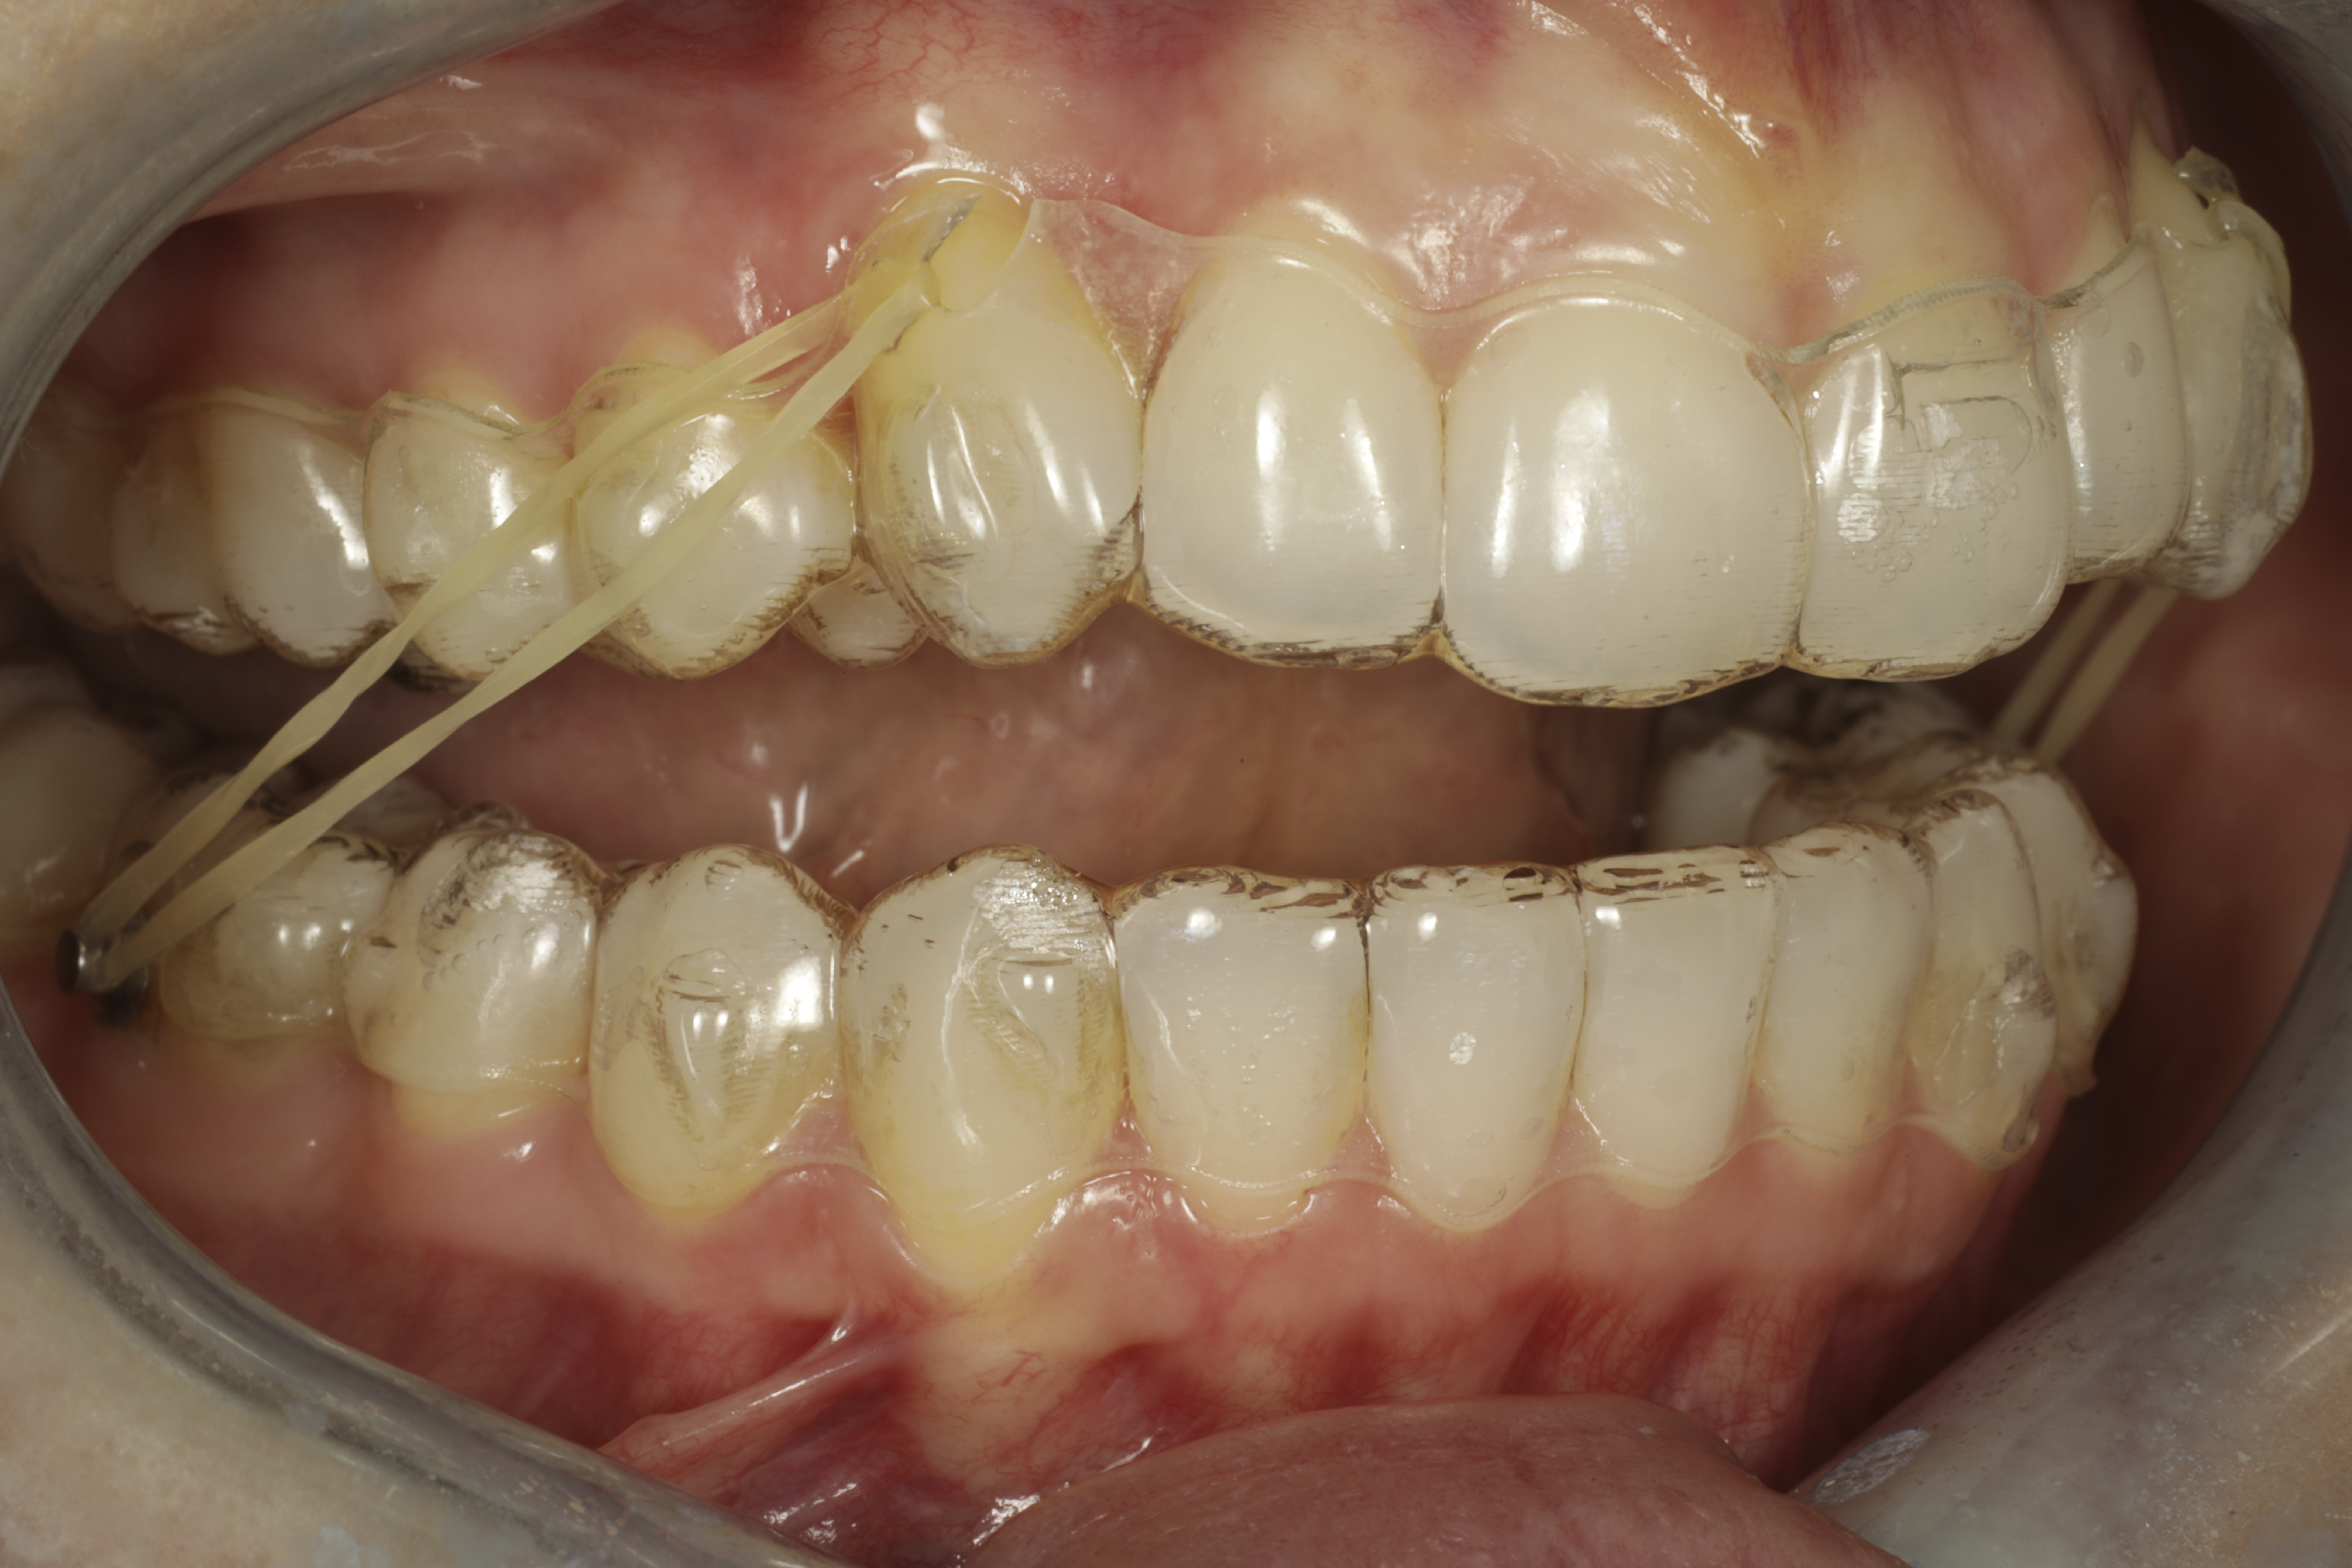

Oikominen aikuisilla on usein ahtautuneiden hammasrivistöjen korjaamista. On neljä tapaa saada lisää tilaa ahtautuneille hammaskaarille. Helpoin tapa on aina työntää ja suoristaa sisäänpäin kallistuneita hampaita ulospäin. Työntyessään ulospäin hampaat luovat hammaskaarelle tilaa. Tätä voidaan tehdä tiettyyn pisteeseen saakka riippuen luun määrästä sekä ikenien tyypistä. Toinen vaihtoehto on poistaa hampaita. Tähän onneksi aika harvoin tarvitsee turvautua koska muita keinoja käytetään ensisijaisesti. Kolmas vaihtoehto on työntää hampaita yksi kerrallaan taaksepäin, tästä käytetään termiä hampaiden distalointi. Tällöin hoitoajat ovat jonkin verran pidempiä ja kalvojen välille pitää luoda linkki lisäämällä niihin pienet kuminauhat molemmin puolin jotta hampaiden liikkeet saadaan suuntautumaan oikein (kts. kuva alla). Distaloidessa hampaita viisaudenhampaat on poistettava koska ne ovat silloin tiellä.

Kuminauhat ja distalointi

Mittaustavasta riippuen kahdella kolmasosalla aikuisista Suomalaisista on jonkiasteinen purentavirhe. Jos yläleuan hampaat ovat alahampaita edempänä, puhutaan mesiaalipurennasta ja toisinpäin distaalipurennasta. Näiden korjaamiseksi kalvoilla on pystyttävä liikuttamaan koko hammaskaaren hampaita suhteessa vastapuolen hampaisiin. Ilman linkkiä kalvojen välillä tämä ei tapahdu.

Yhteys kalvojen välillä luodaan käyttämällä pieniä kuminauhoja. Yleensä kuminauhan toinen pää kiinnittyy poskihampaan pintaan kiinnitettävään nuppiin, ja toinen pää kalvossa kulmahampaan kohdalla olevaan loveen. Näiden avulla tapahtuvaa liikettä kutsutaan distaloinniksi. Kuminauhoja käytetään sama tuntimäärä vuorokaudessa kuin kalvojakin. Ne saavat oikomishoidon näkymään aavistuksen enemmän, mutta normalisti puhuttaessa kuminauhoja on aika vaikea huomata